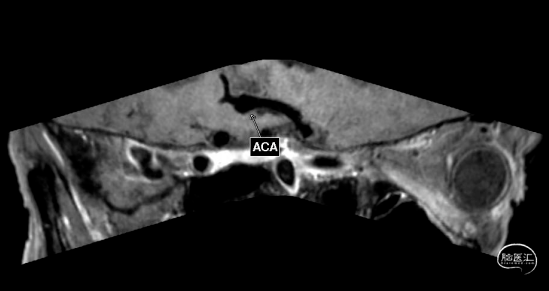

现病史:2+天前,患者饭后突发呕吐,为胃内容物,非喷射性,未见明显咖啡色物体,呕吐后患者自觉头痛胀痛,双额部为主,无肢体抽搐,无意识丧失,大小便失禁等;患者未予重视,未行特殊处理;头痛症状未见明显好转,遂于昨日于当地医院就诊,完善头部MR及CTA提示蛛网膜下腔出血,前交通动脉瘤;予以抗纤溶、止痛等对症处理;患者家属为求进一步治疗,遂120转院至我科,急诊以“前交通动脉瘤破裂伴蛛网膜下腔出血”收入我科。

经测量可得动脉瘤宽度平均值为7.0mm,动脉瘤高度为5.18mm,选用WEB™ SL 8*4。

WEB™经由VIA™微导管送入动脉瘤瘤腔并完全释放。术后即刻造影显示WEB™尺寸合适,贴壁良好,分支等血流通畅。解脱后再次造影,可见动脉瘤瘤腔内有明显造影剂滞留。